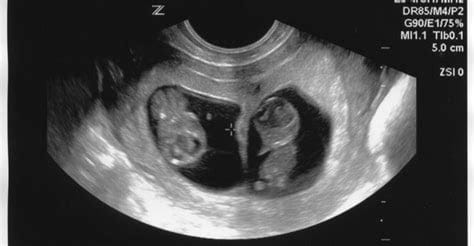

هل يمكن التأكد من الحمل بتوأم بالتحليل المنزلي

لا يقوم التحليل المنزلي إلا بإخبارك أنكِ حامل فقط، لذلك يجب عليكِ التأكد بأنك حامل بتوأم ذكور عن طريق فحص الموجات فوق الصوتية، حيث تقدم لكِ تأكيدًا قاطعًا بأنكِ حامل في توأم، كما أنه يؤكد أعراض الحمل بتوأم بعد الحقن المجهري الذي قمت بإجرائه.

موجات فوق صوتية للحمل بتوأم

مجرد أن يرى طبيبك صور الموجات فوق الصوتية سيؤكد لك عدد الأجنة في الرحم وكونك حاملًا في توأم أم لا، كما يدل ارتفاع هرمون HCG  أيضًا على نجاح الحمل، وتكون قراءته أكبر ما يمكن عند الحمل بتوأم.

ففي حالة قراءة هرمون HCG وكانت 200 وحدة دولية فهذا يدل على أنكِ حامل بجنين واحد، أما إذا كانت قراءته أكبر من 600 وحدة دولية فهذا دليل علي أنكِ حامل بتوأم ويجب عليك التأكد عن طريق فحص الموجات فوق الصوتية.